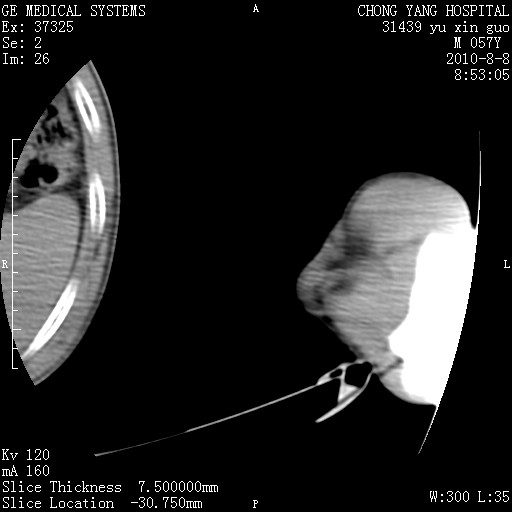

标题: CT28267:M57Y 上臂包块8年余。 [打印本页]

标题: CT28267:M57Y 上臂包块8年余。

包膜光滑、完整的脂肪密度肿块,支持脂肪瘤。